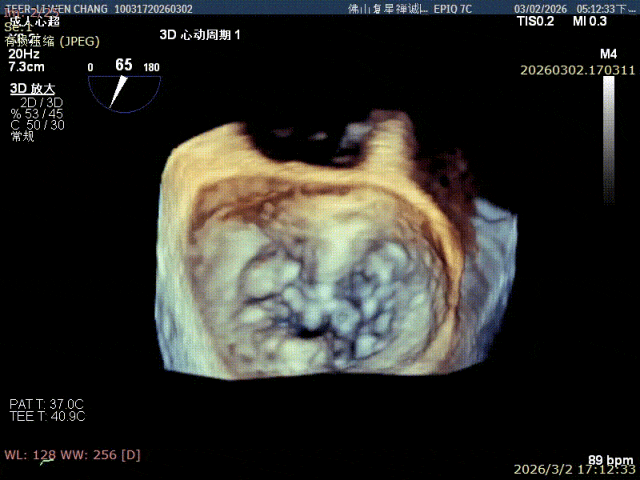

术前影像

3D 1区脱垂